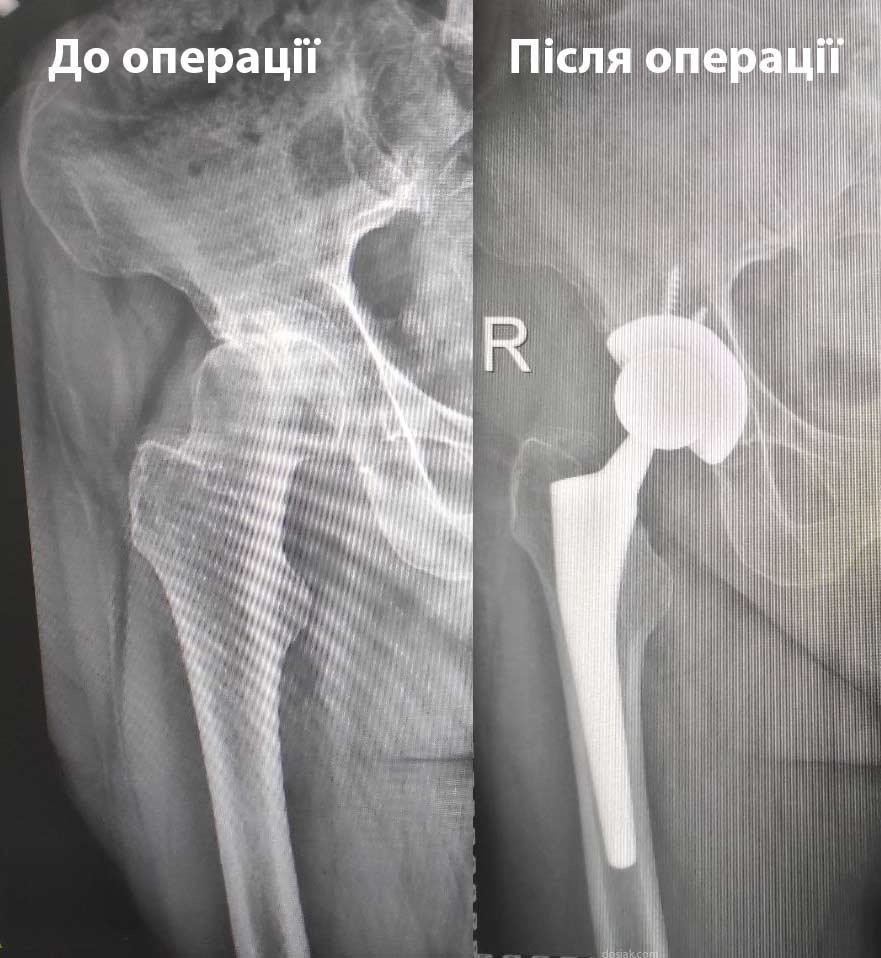

Від щирого серця хочу подякувати хірургу Досяк Мирославу Ігоровичу. Я щиро бажаю Вам успішно продовжувати рятувати своїх пацієнтів, завжди виправдовувати всі добрі надії і неодмінно знаходити вихід з будь-якої ситуації. Здоров’я Вам і Вашій родині, благополучної діяльності і щасливого довгого життя. Спасибі за Вашу працю, за Ваш професіоналізм, за Вашу самовідданість. Також хочу висловити вдячність медсестрі, яка по операції цілу ніч не відходила від мене і зволожувала мої губи. А ще, велике спасибі інтерну Тарасу, який зустрів при поступленні і поміг зробити всі необхідні аналізи в одному кабінеті,щоб не мучити мене,перед операцією. Велике дякую анастазіологу який професійно виконав свою роботу і врахував попередні травми. Загалом Хочу висловити величезну подяку всім працівникам лікарні від санітарочки до хірурга, там працюють чудові люди, які люблять свою професію. Дякую1-ій МІСЬКІЙ КЛІНІЧНІЙ ЛІКАРНІ ІМ. КНЯЗЯ ЛЕВА за Ваших відданих і чуйних професіоналів, за безкоштовні медикаменти та добро, яке вони випромінюють в своїй роботі. А також за чистоту!